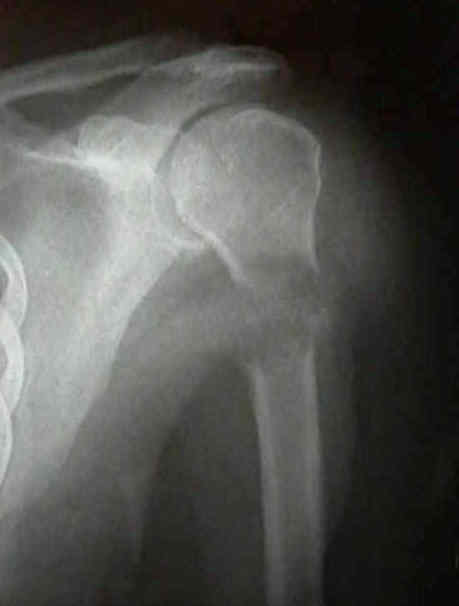

Fémur proximal (cuello y región pertrocanterea), diáfisis femoral, húmero proximal, columna (cuerpos vertebrales).

- Localización: Alto riesgo: Fémur proximal (cuello, subtrocantérea), diáfisis femoral, húmero proximal. Riesgo extremo: Lesiones pertrocantéreas y subtrocantéreas.

| Localización | Miembro superior | Miembro inferior (excepto peritrocanterea) | Región peritrocanterea / cuello femoral |

- Riesgo alto (≥9) o dolor funcional en fémur proximal/húmero: Estabilización quirúrgica profiláctica (clavo intramedular, artroplastia, placa) + RT postoperatoria.

- Fijación Interna con Injerto/ Sustituto: Para fracturas o lesiones en riesgo en huesos largos. Enclavado intramedular bloqueado (fémur, tibia, húmero) es el patrón oro. Permite estabilizar todo el hueso (lesiones múltiples).

- Artroplastia (Prótesis): Indicada en fracturas/lesiones articulares (cabeza femoral, humeral, cóndilos) o con gran destrucción de la metáfisis. Proporciona estabilidad inmediata y permite carga completa.